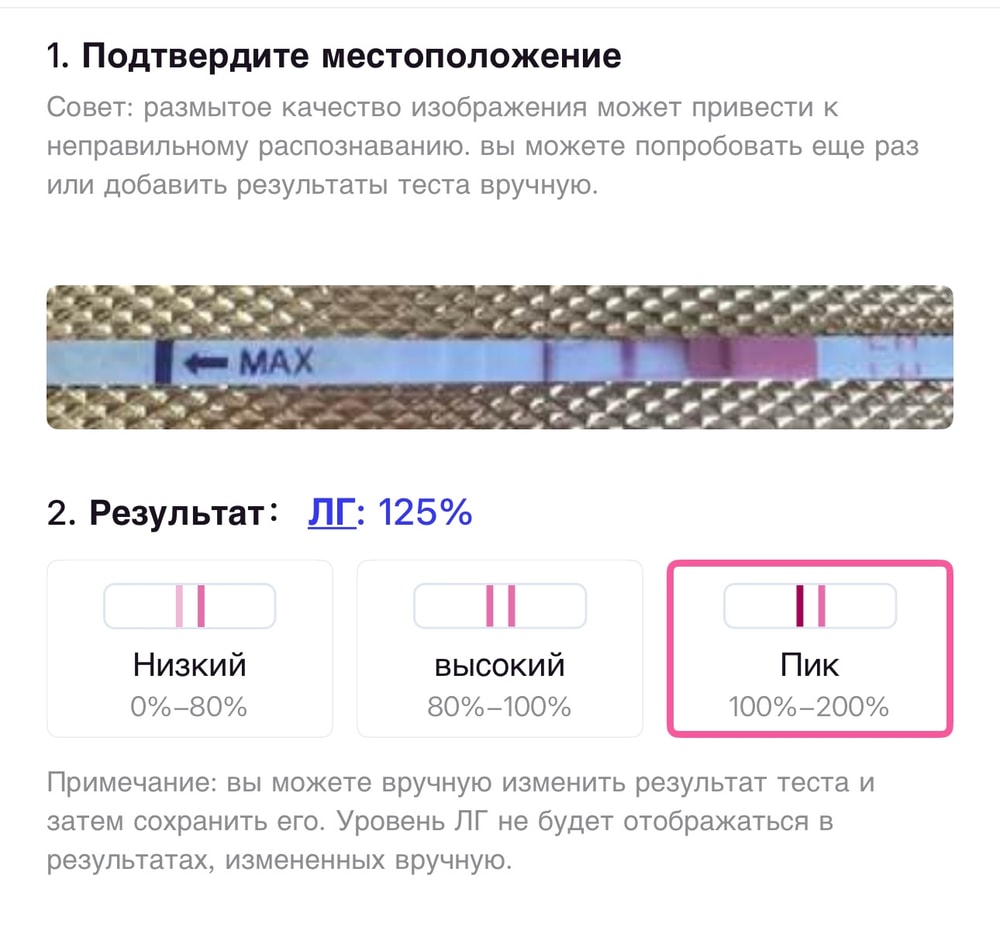

Тесты в студию🤗

Вот и мне отреагентили эти прекрасные тесты.

Что-то я понять не могу, свой организм вместе с тестами на овуляцию.

Тестик на овуляцию ярчает) я радуюсь как ребенок😂 овуляция с СПКЯ, большая редкость. Последняя была в январе (стимулированная), а предпоследняя в мае 2024 года. 20 д.ц и счаст